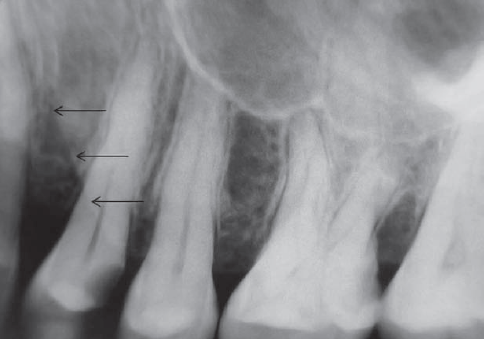

54. What is showing by arrow?

External Oblique Ridge a continuation of the anterior border of the mandibular ramus. It follows an anteroinferior course lateral to the alveolar process.

76. What is B showing?

Internal oblique ridge is the bony protuberance located on the lingual surface of mandible extending diagonally downward from the ramus and ending anteriorly near the apices of the premolars. Its function is to serve as an attachment site for the mylohyoid muscle of the floor of the mouth.

77. What is A showing?